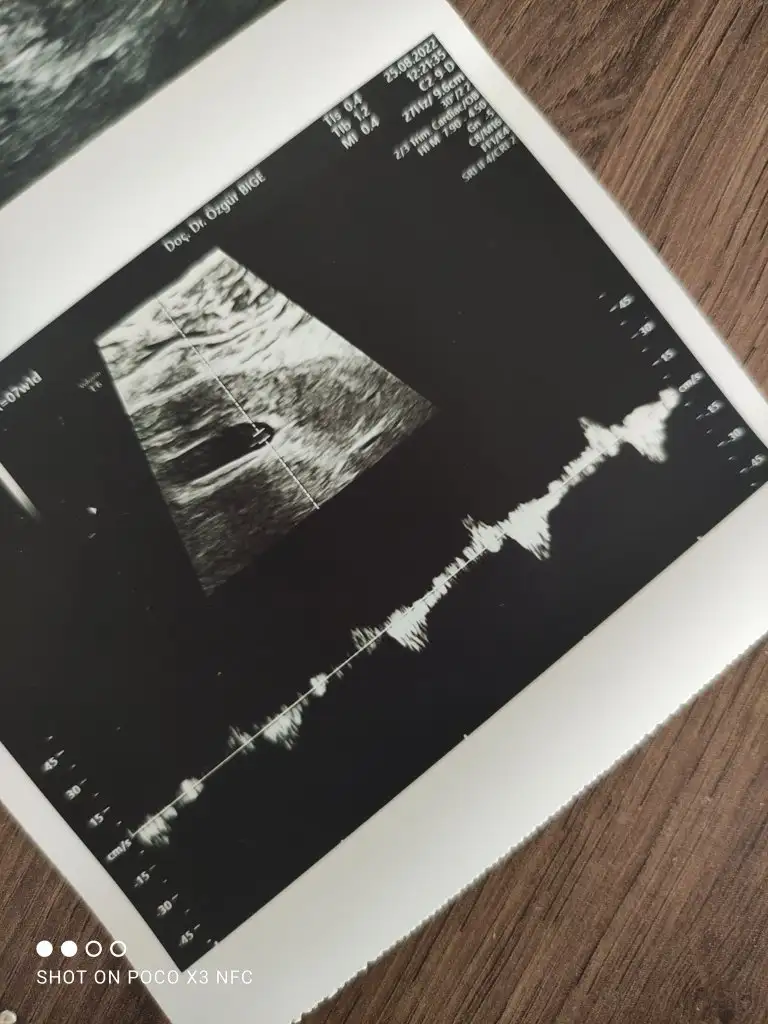

Kalp atışı dakikada 134, soyu 10.8mm 7+1 haftayla uyumlu canım. Maşallah bebişine hep sağlıkla büyüsün.

Benimkinin kalp atım hızı belli mi acaba ya anlayamadım alttaki beyaz şey kalp atımı sanırım

Günaydın kizlar 🌺 bugün yine doktora kontrole geldim. Çünkü kanamalarım bitmiyor. Yine kanamam oldu bayağı kırmızı adet olmuş gibi kanama hem de. Doktoru aradım hemen gel dedi. Maşallahı var bebiş gayet iyi büyümüş kolları bacakları bile çıkmış. Hiçbir sorun görmedi yine. Geç döllenmeden dolayı bir hafta geri geldik 7 haftalikmis. Ultrason fotoğrafı i paylaştım yazıları çok anlamıyorum kalp atışı falan nedir boyu hangisi yardımcı olur musunuz?